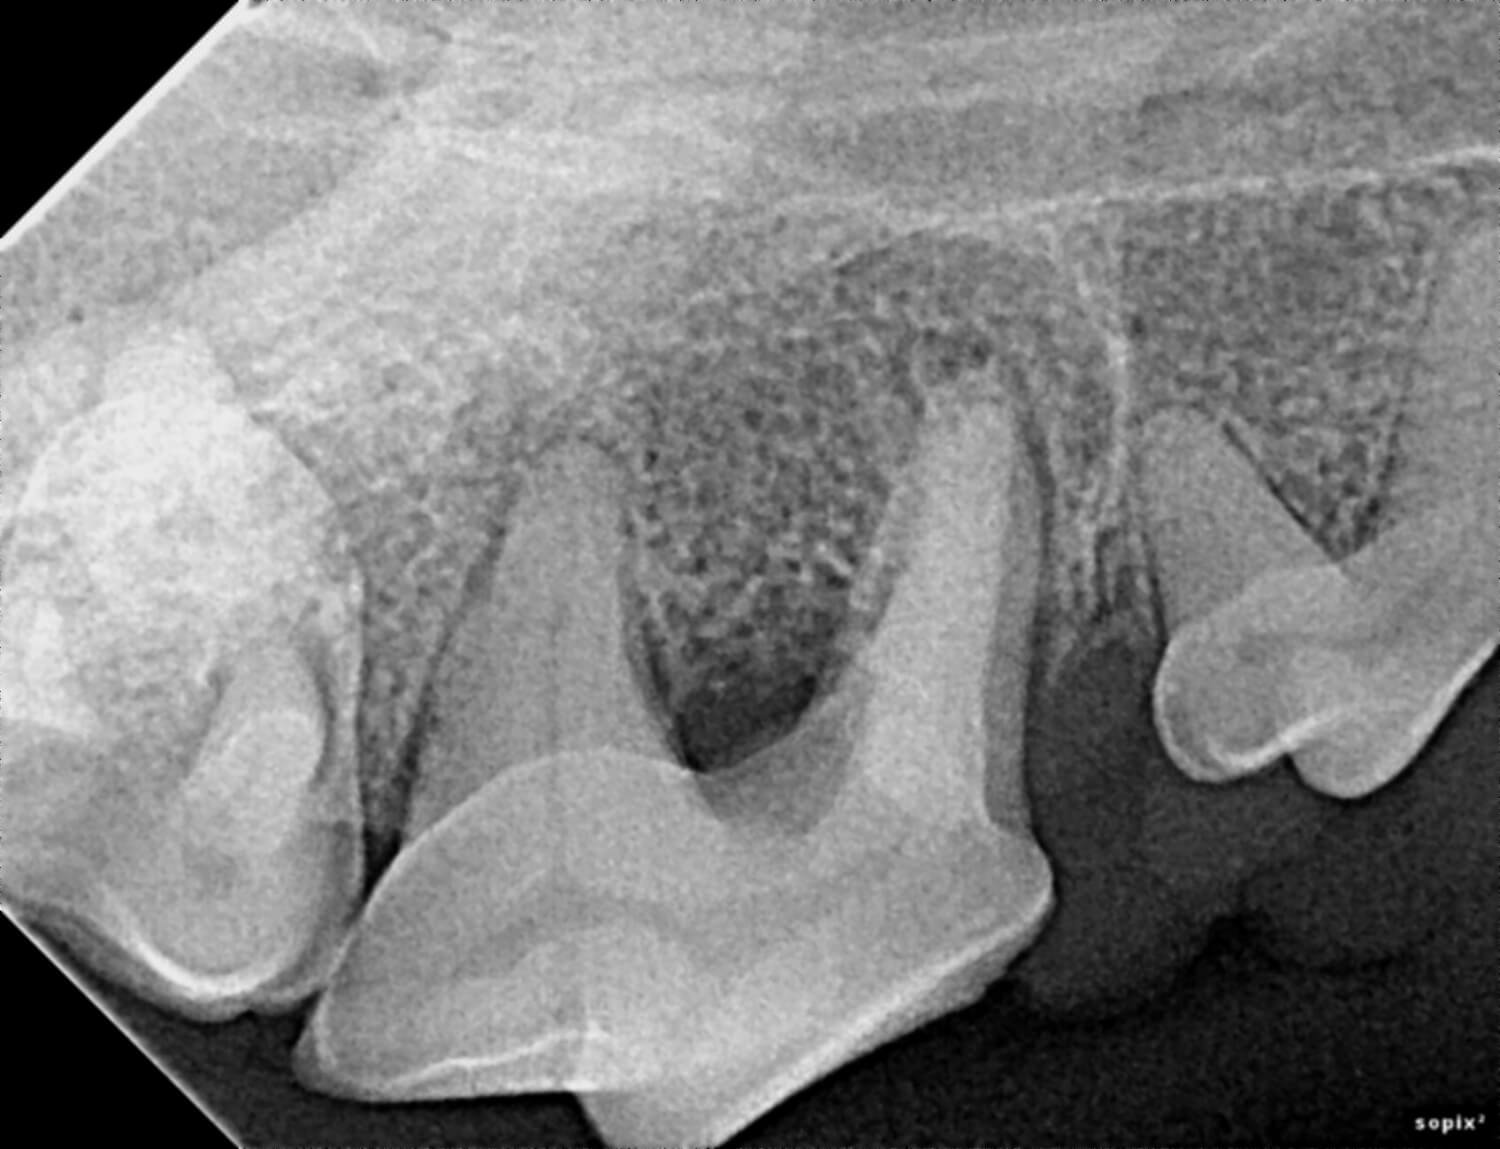

Our veterinarians use digital radiology to detect conditions such as tooth root abscesses, oral tumors, jaw fractures and hidden dental and periodontal issues. Early diagnosis enables timely treatment, reducing pain and preventing advanced dental complications.

Digital radiology plays a vital role in preventive health and advanced diagnosis for pets. Dental and oral conditions are often hidden below the gumline, where physical exams cannot detect them.

This imaging can reveal issues such as periodontal disease, infections, tooth resorption, and bone loss before they cause noticeable pain or lasting damage. Prompt diagnosis allows our team to provide targeted treatments that keep your pet comfortable and healthy.

Digital radiology helps identify dental and oral problems in their earliest stages, often before visible symptoms develop. This means less invasive treatments and better outcomes for your pet.

Precise imaging guides our veterinarians in planning surgical or dental procedures for maximum safety and effectiveness. Detailed X-rays also support ongoing monitoring for chronic conditions.